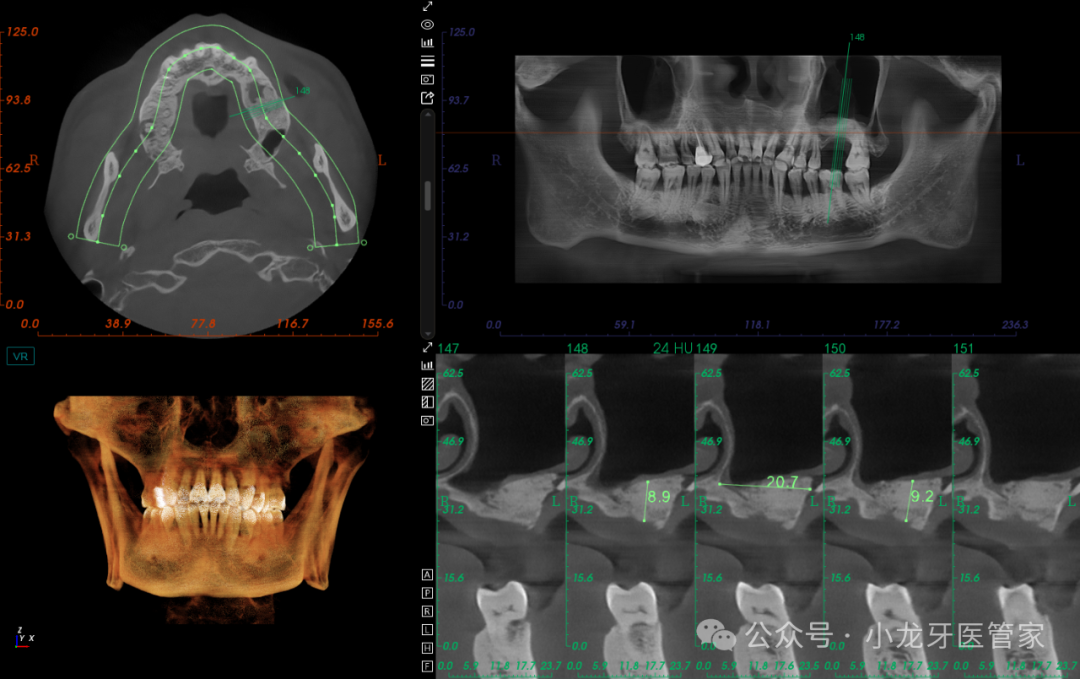

种植一期手术:

患者知情同意并签署《口腔种植修复知情同意书》。常规消毒铺巾,4%阿替卡因局部浸润麻醉,26缺牙区牙槽嵴顶作水平切口,全层切开粘骨膜,翻瓣,发现缺牙区骨面平坦,整体骨质较硬(III类骨),定位,先锋钻备洞至预定深度,扩孔钻逐级扩孔,制备种植体窝,置入ITIblt骨水平种植体,型号:4.8mm*10 mm,植入扭矩35N.cm,旋入覆盖螺丝。减张缝合。

术后影像学图片